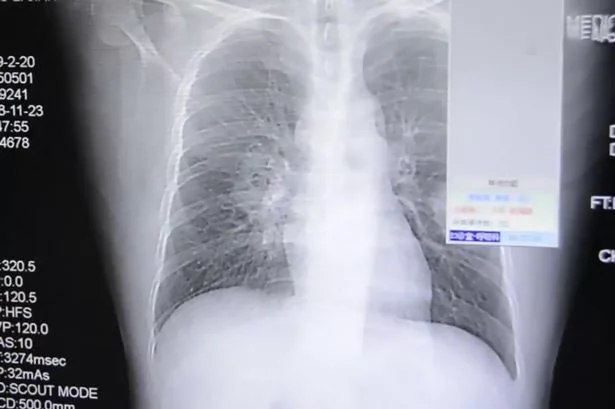

5. Pria ini dapat infeksi paru-paru akibat cium kaus kaki sendiri

Pria ini dapat infeksi paru-paru akibat cium kaus kaki sendiri